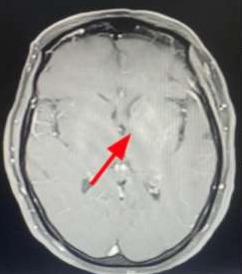

The cranial CT scan reveals a supratentorial intra-axial lesion adjacent to the left lateral ventricle body. It appears spontaneously hyperdense, rounded, well-defined, with heterogeneous enhancement after contrast administration. The lesion measures 11 x 9 mm and is associated with cortical veins draining into the deep collector vein. There is hyperdensity of the basal ganglia, more pronounced on the left, consistent with toxic/metabolic encephalopathy. Subsequently, a cranial MRI is performed, which indicates findings consistent with a left periventricular cavernoma. There are no signs of current complications, with an associated venous anomaly of development. Hyperintensity on T1-weighted images is observed at the head of the left caudate nucleus and lentiform nucleus, which do not enhance with gadolinium. These alterations in the left basal ganglia are compatible with non-ketotic hyperglycemic hemichorea.

Figure 2: Cranial MRI showing hyperintensity on T1-weighted images at the level of the head of the left caudate nucleus and lentiform nucleus, which do not enhance with gadolinium